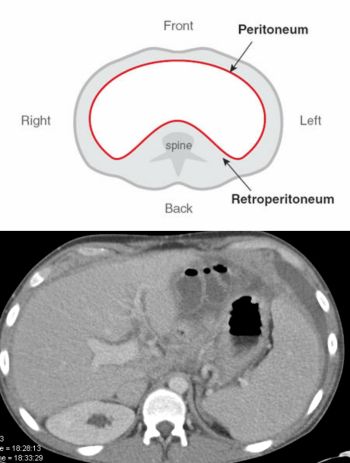

Mide, bağırsaklar, karaciğer, dalak ve pankreas gibi iç organları örterek karnın içini kaplayan torba; periton. Karın zarı ya da peritoneum (ya da periton) abdomen ve pelvis boşluğu duvarlarının iç yüzünü ve bu boşlukta yer alan tüm organları saran veya örten zara verilen isimdir. İç organlardan böbrekler ve böbreküstü bezleri karınzarının dışındadır. Çok ince olduğu hâlde yer yer güçlü bükümler oluşturur ve birçok organı yerinde tutan bağlar bu biçimde oluşur. Karın içindeki organlar, insan duruşunu değiştirirken biraz sağa sola kayabilirler. Bir organın hastalık nedeniyle büyümesi ya da küçülmesi durumunda, komşu organlar da durumlarını yeniden ayarlamak zorundadır. Periton zarının yüzeyinin sürekli kaygan olması nedeniyle komşu organlar birbirleri üzerinde rahatlıkla hareket edebilirler.

İki kısımdan oluşur:

- Karın ön ve arka duvarlarının iç, diyaframın alt ve pelvis boşluğunun üst yüzünü saran bölümüne peritoneum parietale adı verilir.

- Karın arka duvarından ve diyafram bazı bölgelerde ayrılarak, iç organların bir kısmını veya tamamını saran bölümüne ise peritoneum viscerale denir.